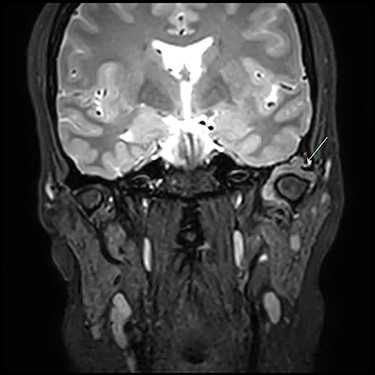

A 33-year-old woman complained of a 3-month history of left-sided TMJ morning stiffness. She had never been treated nor undergone any previous TMJ procedures and reported an unremarkable medical history. Examination findings showed a small left-sided preauricular swelling with tenderness worse at the joint level. Mouth opening restricted by pain was 35 mm. Normal excursive movements and no malocclusion or lateral deviation was observed. Computed tomography (CT) and magnetic resonance imaging (MRI) of the TMJs showed: superior joint space effusion, multiple small low-signal intensity foci within the fluid and extensive erosions within the glenoid fossa, articular eminence and root of the zygoma (Figs 1 and 2). This was reported to be highly suggestive of left-sided TMJ synovial chondromatosis.

Post-gadolinium T2 MRI TMJs. Coronal view showing marked distension of the superior joint compartment with extensive scalloped lobulated erosion of the left temporal bone (green arrow).